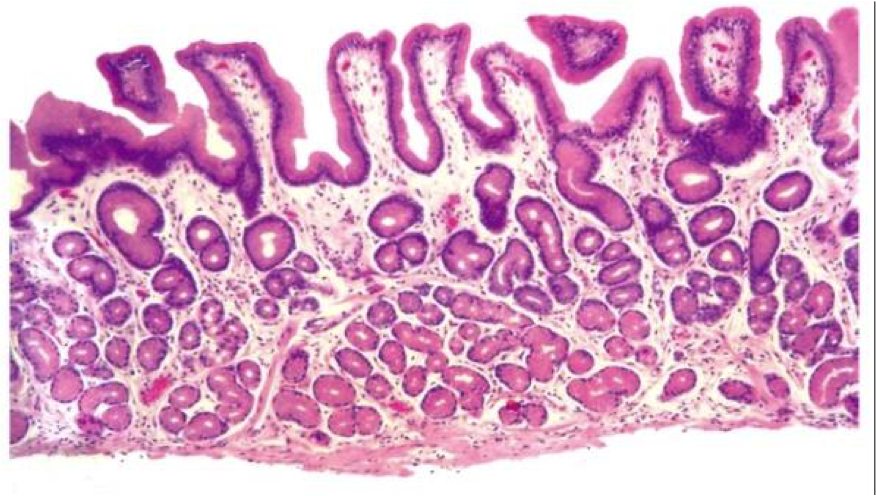

Cardia and Antrum

Cardiac/antral glands

Mucus cells